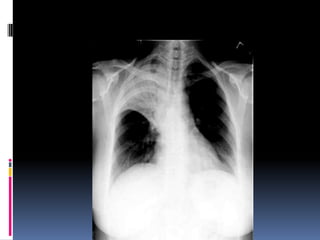

Underpenetrated Film

Hemi diaphragms are obscured

Pulmonary markings more prominent than they actually

Over penetrated Film

 Lung fields darker than

normal—may obscure subtle

pathologies

•   See spine well beyond the

diaphragms

•   Inadequate lung detail

Underpenetrated Film Hemi diaphragmsare obscured Pulmonary markings more prominent than they actually

Over penetrated Film Lung fields darker than normal—may obscure subtle pathologies • See spine well beyond the diaphragms • Inadequate lung detail